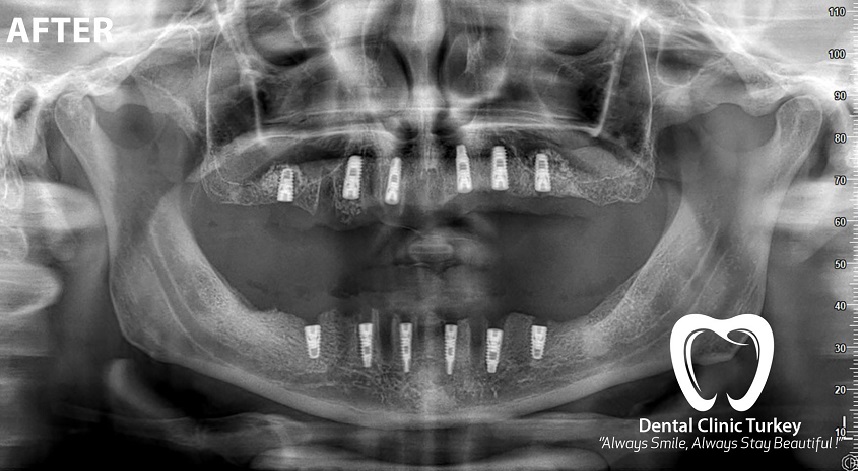

Les implants sont des vis en titane qui sont placées dans l’os de la mâchoire pour remplacer les dents manquantes. Les prothèses dentaires préparées dans des environnements stériles sont placées sur des vis insérées dans l’os. Pour que le traitement implantaire soit effectué, il est nécessaire d’avoir une structure osseuse adaptée. Des interventions chirurgicales osseuses sont également effectuées pour les os inadaptés. Les prix des implants varient en fonction de toutes ces procédures.

Bien que les prix des implants soient relativement élevés, les dents sur implants donnent les résultats les plus proches des dents naturelles. Car les dents implantées ne reçoivent pas de soutien d’autres dents, elles tirent leur force de l’os de la mâchoire comme les dents naturelles. Dans l’application d’implant, la gencive est d’abord ouverte et un trou est fait dans l’os de la mâchoire. Ce trou est suffisamment large pour que l’implant s’adapte. L’implant est placé et la partie gingivale au-dessus de l’alvéole dentaire ouverte est refermée et l’implant devrait fusionner avec l’os de la mâchoire.

Si l’os de la mâchoire n’est pas suffisant, il est nécessaire de faire une greffe osseuse, c’est-à-dire de renforcer l’os de la mâchoire. Apres la greffe osseuse, une période de 2 à 3 mois est nécessaires pour que l’implant s’intègre à l’os de la mâchoire. L’application d’implants est en fait très facile, mais c’est un travail qui nécessite des connaissances techniques et médicales élevées. Ainsi, du point de vue de ceux qui sont traités, Le patient vient et repart avec de nouvelles dents en quelques étapes.

Pour commencer, le médecin examine le patient et analyse la structure de la mâchoire et de l’os. Ensuite, il indique si le patient est apte à recevoir un traitement implantaire. Ainsi on peut commencer la phase de pose des implants. L’implant est placé sous la gencive. Ensuite, il faut attendre un moment que l’implant et l’os de la mâchoire fusionnent. Une vis de cicatrisation est ensuite placée sur l’implant. Après la récupération, les répétitions nécessaires sont faites et pour finaliser la couronne en porcelaine est ensuite placée sur l’implant.

L’élément principal pour lequel les patients sont curieux de savoir ce qu’est un implant peut également être le stade de la pose de l’implant. Cette opération peut être effectuée par 2 méthodes différentes. La première consiste à installer un capuchon (vis chirurgicale) temporaire immédiatement après la pose de l’implant. Dans la deuxième méthode, l’implant est placé et refermé avec la gencive. On s’attend à ce que la récupération ait lieu pendant un certain temps. Après cela, le processus d’installation des dents prothétiques est effectué. Une fois la vis en titane insérée, il faut attendre 3 mois pour la mâchoire inférieure et 4 à 6 mois pour la mâchoire supérieure. Grâce à cela, une récupération complète est obtenue.